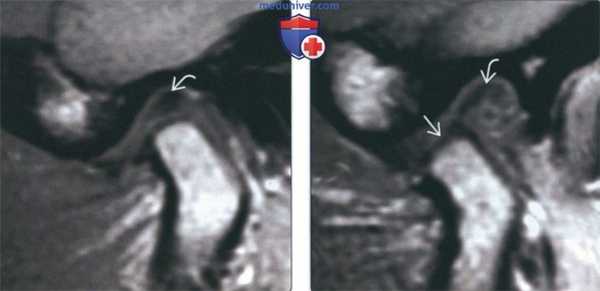

(Слева) На серии из восьми изображений ВНЧС показано положение компонентов сустава при «чистом» переднем смещении диска с редукцией в процессе открывания и закрывания рта. Мыщелок занимает слегка более заднее и верхнее положение в суставной ямке вследствие отклонения толстого заднего пучка от его нормального положения на 12 часах относительно мыщелка.

(Справа) Начинается ротация мыщелка, сопровождающаяся легким расширением верхнего отдела суставного пространства. Диск «начинает» выдавливаться кпереди. (Слева) Начинается трансляция мыщелка, сопровождающаяся расширением верхнею отдела суставного пространства, в т.ч. сзади. Диск продолжает «выдавливаться» кпереди и деформируется (изгибается), растягивая переднюю стенку капсулы.

(Справа) Диск возвращается обратно мыщелком, проходящим по заднему диску и вставляющимся в промежуточную зону диска, приводя к щелчку. Определяется расширение кровеносных сосудов в задисковых тканях, наблюдаемое в норме при трансляции мыщелка. (Слева) Продолжается трансляция мыщелка по диску (к границе нормальной подвижности).

(Справа) Во время начальной фазы закрывания рта диск и мыщелок остаются в положении редукции, диск имеет относительно нормальную (двояковогнутую) форму.

(Слева) Мыщелок не полностью находится в суставной ямке, но диск остается в нормальном положении.

(Справа) В завершающей стадии закрывания рта до момента контакта зубов мыщелок находится в суставной ямке, а диск смещается вновь, обусловливая более мягкий щелчок закрытия рта. Задние связки диска растянуты и находятся в положении между 11 и 12 часами относительно мыщелка. (Слева) На косой сагиттальной PD МРТ (с закрытым ртом) визуализируется смещенный кпереди диск, задний пучок, которого находится на 10 часах относительно мыщелка. На более медиальном срезе диск занял нормальное положение. Следовательно, речь идет о частичном смещении диска.